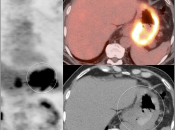

• The utility of PET/CT lies in its assessment of regional nodes and distant metastatic disease.

• Distant Disease: Most commonly to the liver, peritoneum, lung and bone.